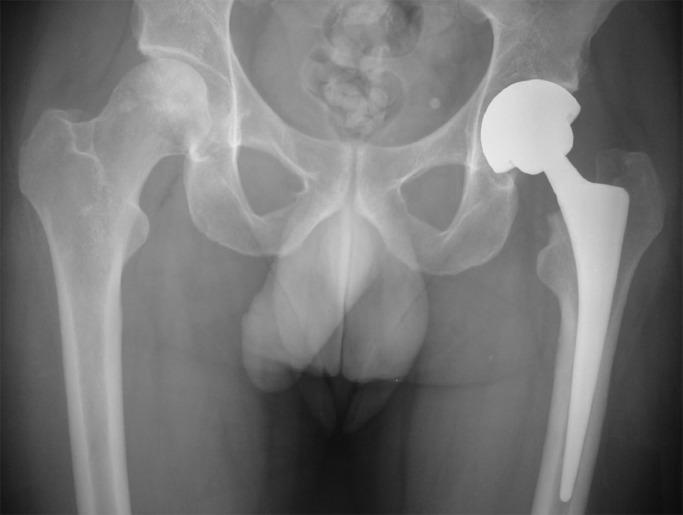

Recovery from COVID-19 is not always uneventful, especially in critically ill hospitalized patients. Persistent symptoms including fatigue/ weakness, shortness of breath, anxiety, and depression have been described at one-year follow-up. Furthermore, symptoms from the musculoskeletal system like joint pain or stiffness are underreported in studies with long-term follow-up of up to one year. Infection with SARS-CoV-2 itself has been associated with endothelial damage, and together with high-dose corticosteroid treatment, it is predisposed to the dissemination of microthrombi and the development of femoral head osteonecrosis (FHOn), as it has been shown during the previous (2003-2004) coronavirus outbreaks. A resurgence of FHOn cases is anticipated but this is not reflected in the existing studies with long-term follow-up. Prompt diagnosis is critical for early treatment and possibly for the hip joint preservation. Patients with COVID-19 treated with corticosteroids should be screened for avascular necrosis early after discharge from the hospital. Every healthcare worker involved in the management of these patients should maintain a high level of suspicion and should be alert when patients report symptoms such as vague aches at the buttocks, hip area, adductors, and/or above the knee. Studies are needed to identify risk factors for FHOn including disease severity, type of steroid, cumulative dose, and duration of treatment.